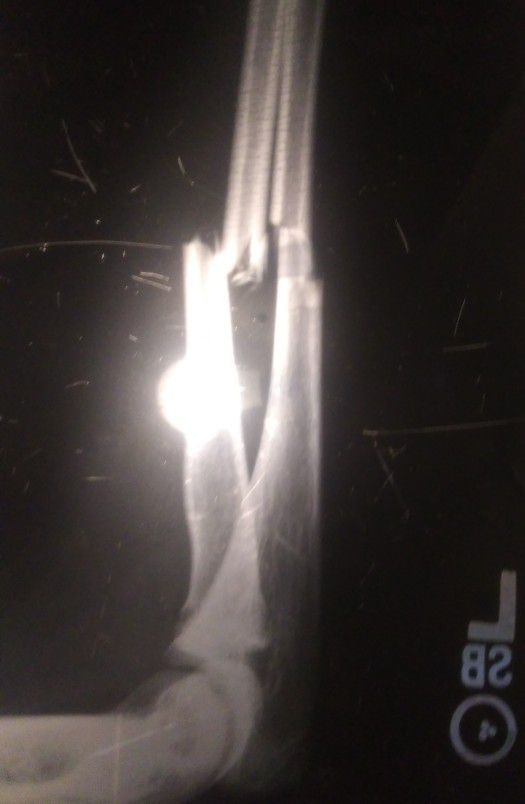

Mid-shaft fracture of the radius and ulna. Ulna looks like a simple spiral fracture.

Exactly what radiologist said what treatment do you propose?

Internal fixation with plate placement. We like longer plates due to the high torsional stress in the forearm.

Patient did well post op and correct